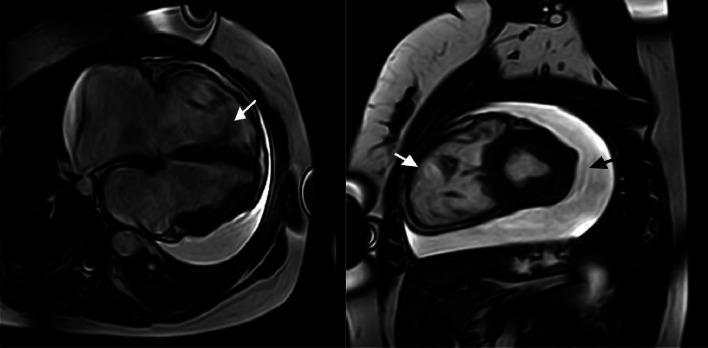

Arrhythmogenic right ventricular cardiomyopathy (ARVC) is a rare but potentially life- threatening genetic disorder characterized by fibrofatty myocardial replacement, ventricular dysfunction, and arrhythmias. Presenting a significant diagnostic challenge due to its phenotypic heterogeneity. While the cardinal features of ARVC are electrical instability and an elevated risk of sudden cardiac death, pericardial effusion, an infrequent manifestation of ARVC, potentially arising from complex interactions between myocardial remodeling and local inflammatory processes, can obscure the underlying cardiac pathology, causing a delayed recognition of the disease. We report a case of recurrent unexplained pericardial effusions in a young female patient presenting with dyspnea and chest pain. Clinical examination revealed muffled heart sounds. Despite initial management with colchicine, the effusion progressed, requiring pericardiocentesis, yielding sero-hematic transudate with negative infectious, cytological, and autoimmune workups. Transthoracic echocardiography revealed a dilated right ventricle with severe tricuspid regurgitation. Cardiac MRI confirmed right ventricular akinesia, an RVEF <40%, and prominent trabeculations. Based on the 2010 Task Force criteria, the diagnosis of arrhythmogenic right ventricular cardiomyopathy (ARVC) was definitively established. This case highlights the importance of considering ARVC in patients with unexplained recurrent pericardial effusions and right ventricular abnormalities, even in the absence of typical arrhythmic symptoms.

致心律失常性右室心肌病(ARVC)是一种罕见但可能危及生命的遗传性疾病,其特征为心肌纤维脂肪组织替代、心室功能障碍和心律失常。由于其表型异质性,带来了重大的诊断挑战。虽然ARVC的主要特征是电不稳定和心脏性猝死风险升高,但心包积液作为ARVC的一种罕见表现,可能源于心肌重塑与局部炎症过程之间的复杂相互作用,会掩盖潜在的心脏病理情况,导致疾病的诊断延迟。我们报告一例年轻女性患者反复出现不明原因的心包积液,伴有呼吸困难和胸痛。临床检查发现心音减弱。尽管最初使用秋水仙碱治疗,但积液仍进展,需要进行心包穿刺术,抽出的是血清血性漏出液,感染、细胞学和自身免疫检查均为阴性。经胸超声心动图显示右心室扩张,伴有严重的三尖瓣反流。心脏磁共振成像证实右心室运动减弱,右室射血分数<40%,小梁明显。根据2010年工作组标准,明确诊断为致心律失常性右室心肌病(ARVC)。该病例强调了在不明原因反复出现心包积液和右心室异常的患者中考虑ARVC的重要性,即使没有典型的心律失常症状。